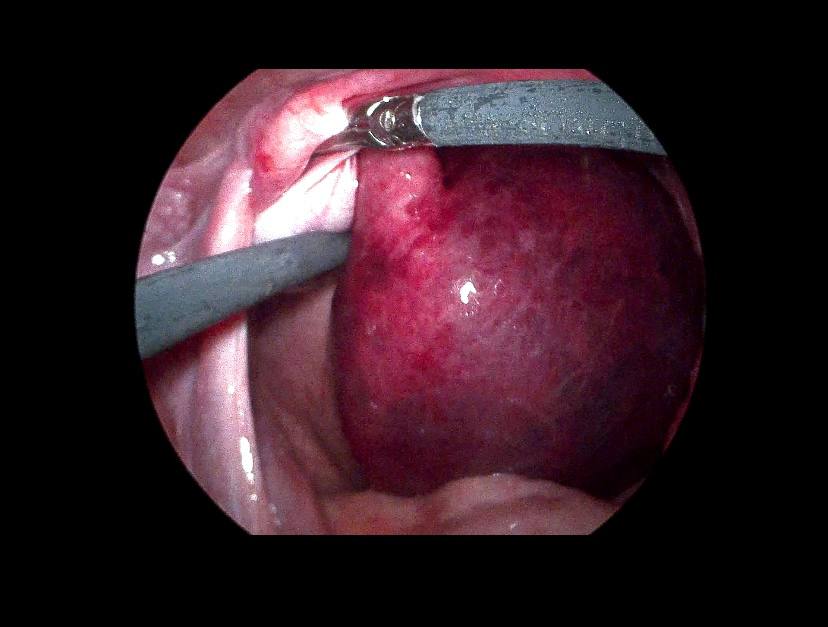

Left ovarian avascular cystic mass 71x68mm , with adjacent left adnexal mass 30x30mm , picture mostly of twisted ovarian pedicle , associated with free fluid >40ml , please for further study to excluded other pathology

Lt ovary is enlarged and edematous, contains 7cm thin wall unilocular cyst “ORADS 1”, there is twisting of its vascular pedicle, picture of ovarian torsion.

operation